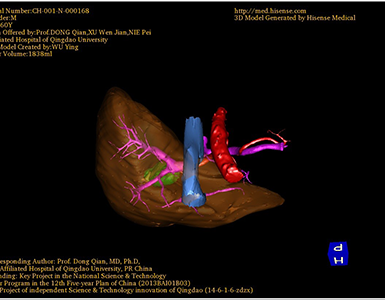

将0.625mm双源薄层CT资料的静脉期和动脉期Dicom格式文件导入海信CAS系统。

通过调节窗宽窗位调整CT序号,对肿瘤,肝实质,胆囊,下腔静脉,肿瘤,肝动脉、门静脉及肝静脉等进行三维重建;系统自动计算肿瘤体积和肝脏体积。

术前手术方案的规划。

术前三维重建:

重建图片